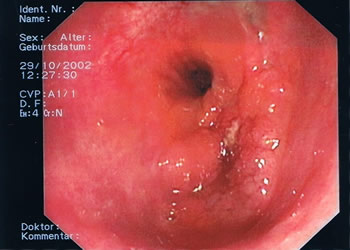

Endoskopische Bilder. Das Darmlumen innerhalb der einzelnen Darmabschnitte kann eher rundlich, leicht eingeengt oder dreieckförmig aussehen, entsprechend des anatomischen Aufbaus (s. Abb.1-4). Grundsätzlich gibt es verschiedene Arten von Polypen mit unterschiedlichen Konfigurationen und von verschiedener Größe. Kugelig(Abb.6) mit schmaler Verbindung zur Darmwand, hügelig mit breiter Basis, muschelförmig, die sich häufig an eine Querfalte anschmiegen, gestielte Polypen, die über einen Stiel mit der Darmwand verwachsen sind und sessile Polypen (Abb.5), die breitbasig auf der Darmwand aufsitzen. Der Übergang zum Dünndarm (Ileocaecal-Klappe) kann des Öfteren ein polypöses Aussehen vortäuschen (Abb.4).